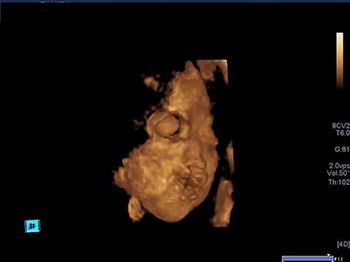

Challenge your diagnostic skills with these images of a third trimester pregnancy. Can you identify the "incidental" findings?